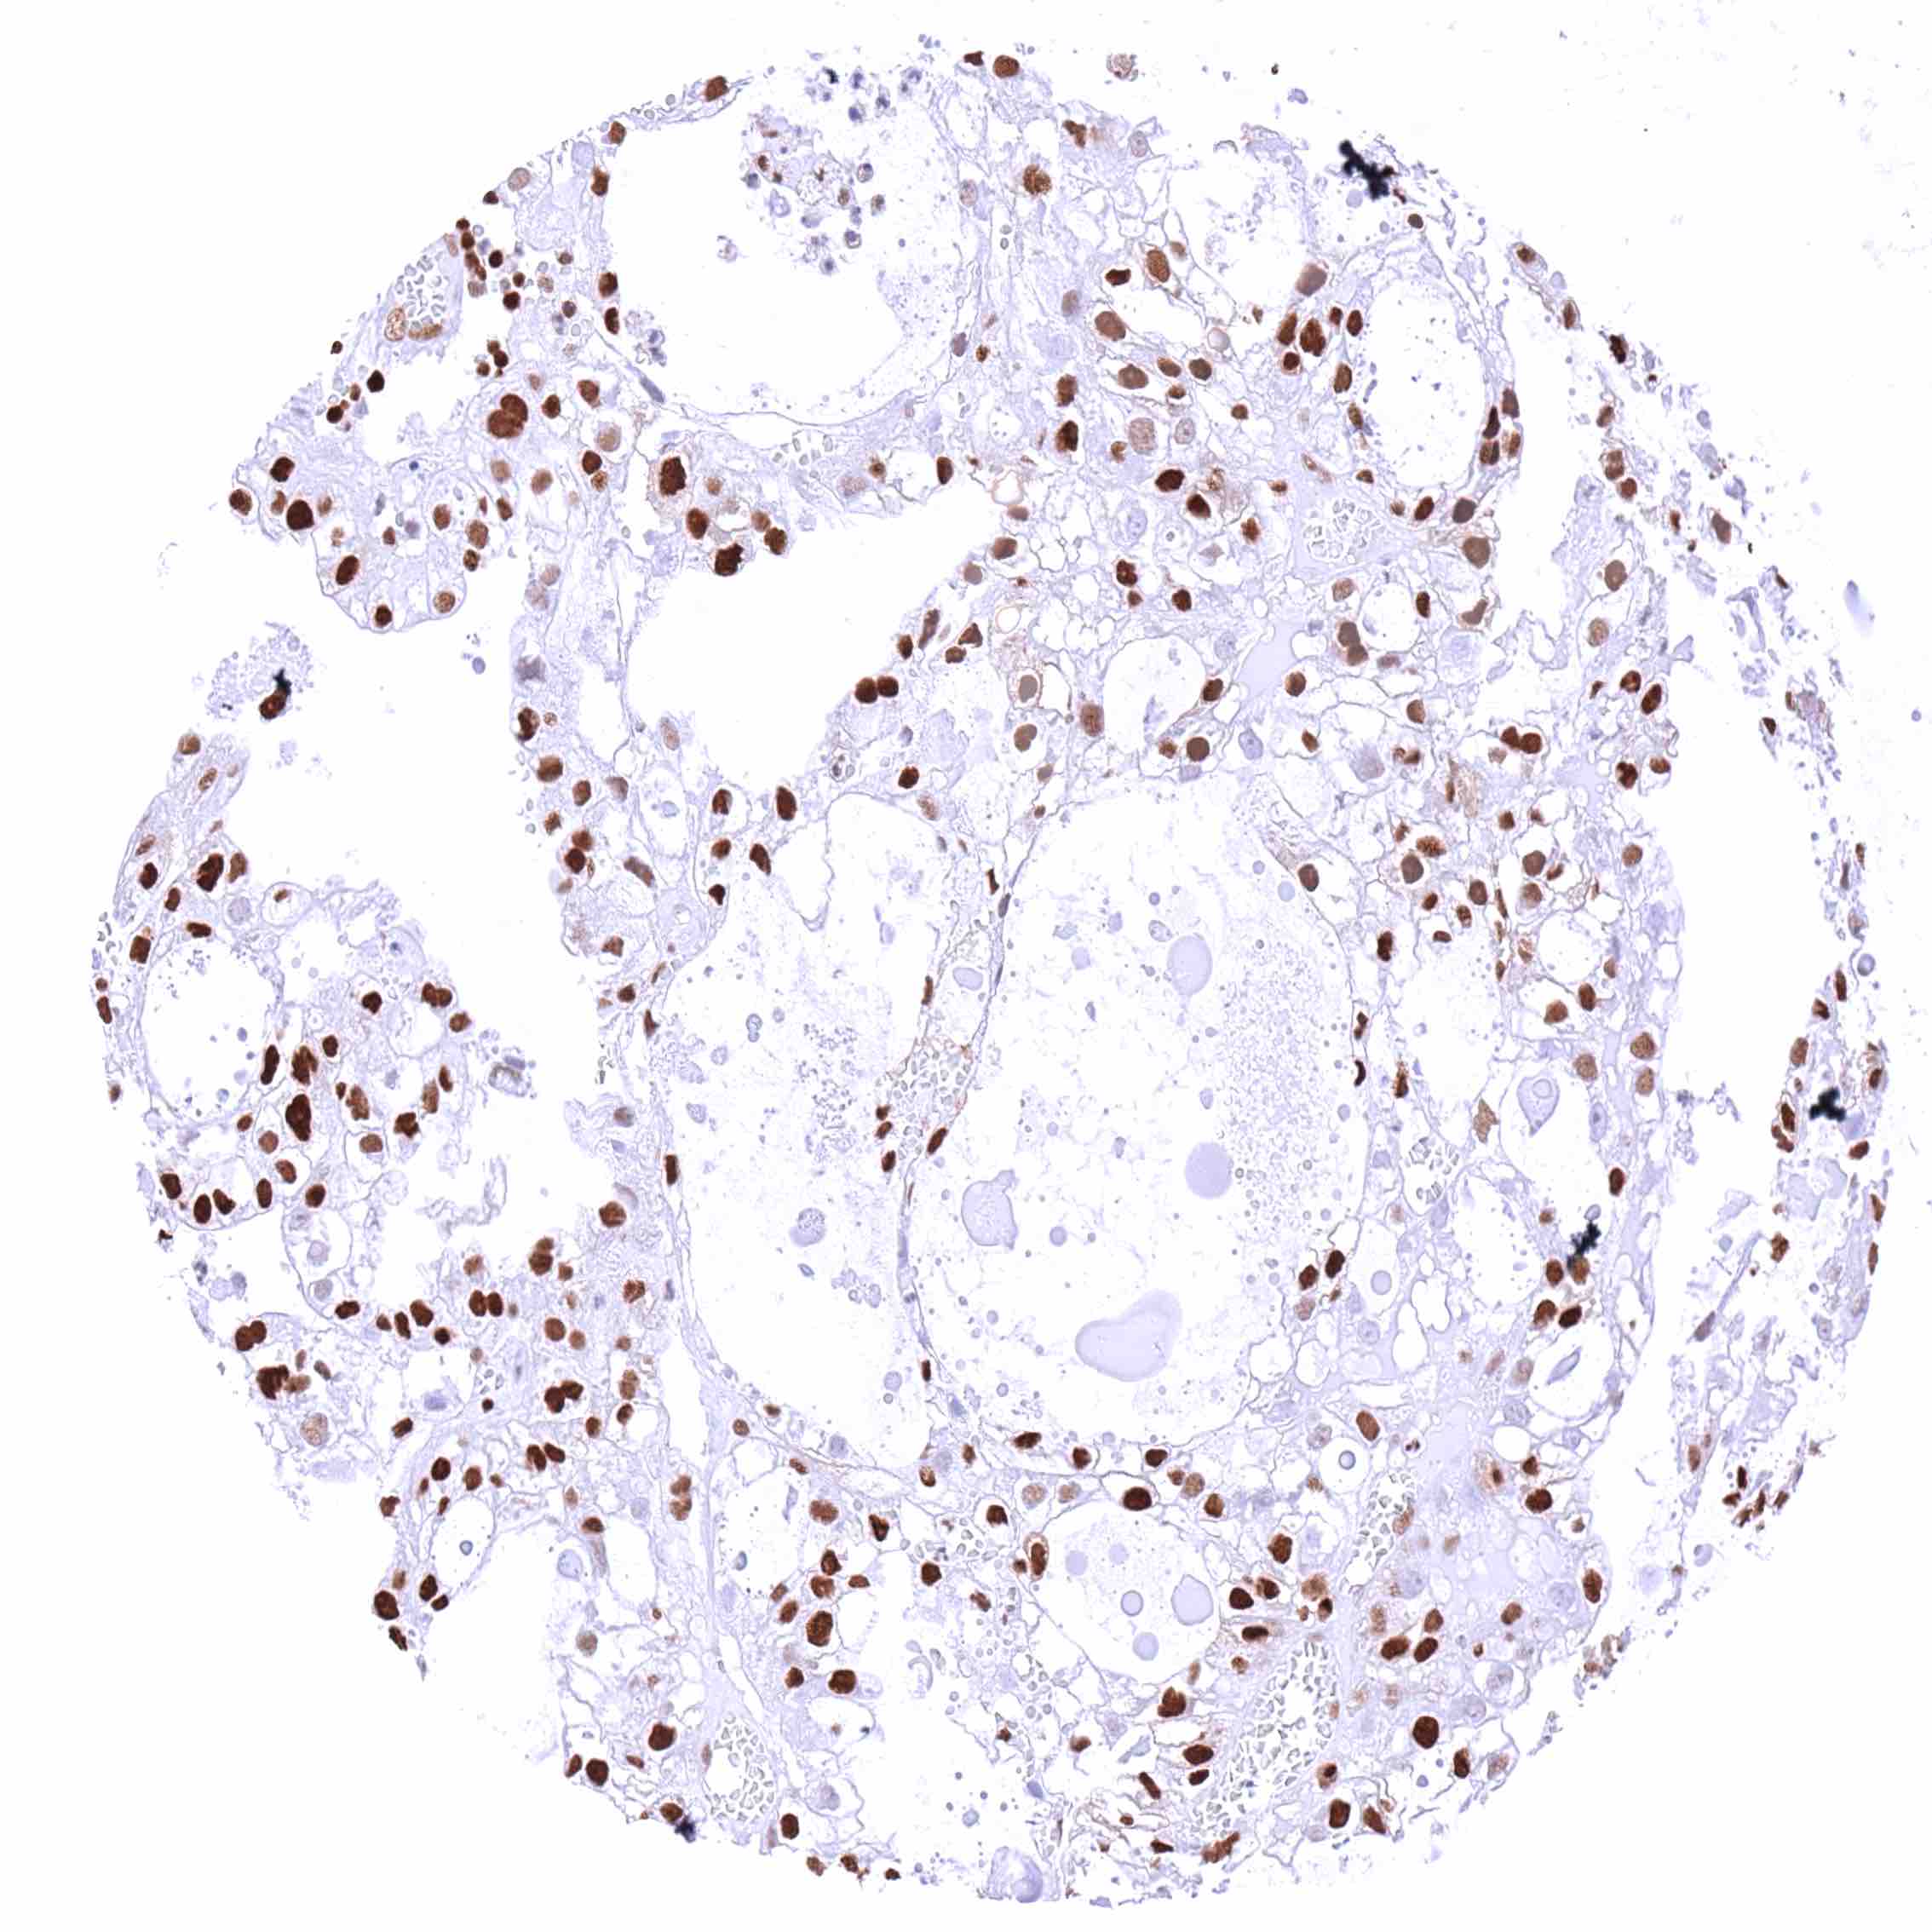

Lung – Adenocarcinoma with faint p27 staining of few tumor cells. Strong p27 positivity of stroma cells.